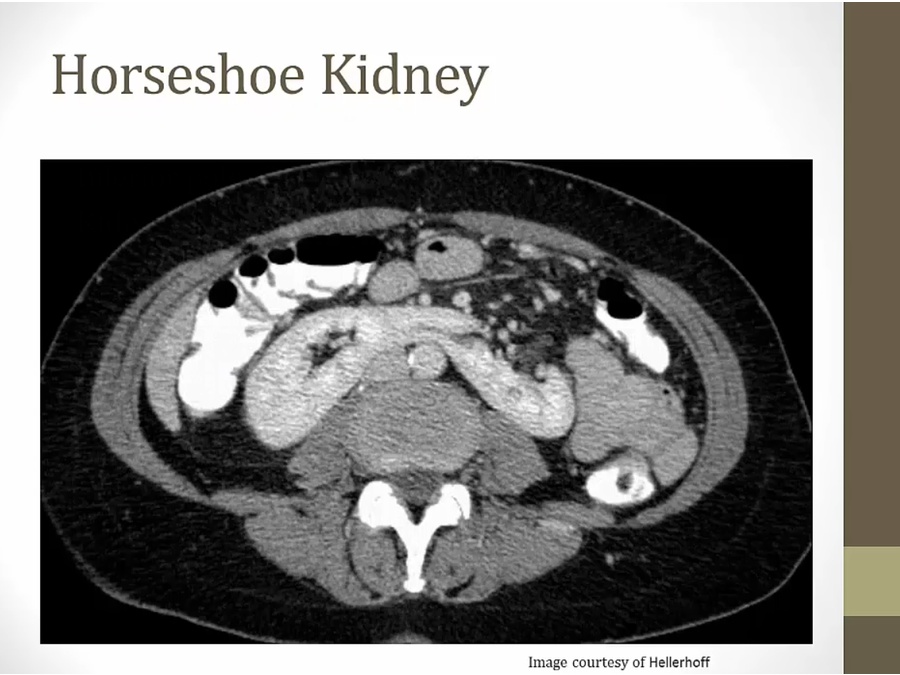

can't rise in abdomen